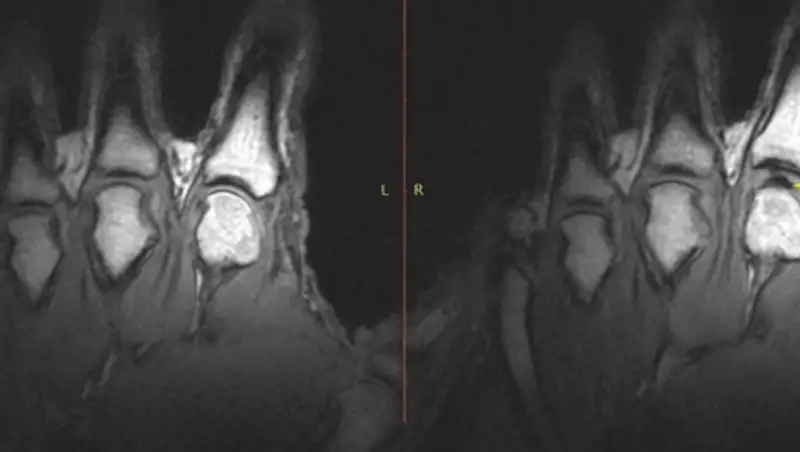

Талантливые пальцы мастера исследователи поместили в специальные трубки, которые осторожно вытягивали их, пока тот неподвижно лежал в томографе, – и тем самым заставляли хрустеть. Весь процесс разворачивался около 300 мс и впервые предстал изумленным глазам ученых во всех деталях.

Коротко говоря, наблюдения подтвердили первоначальную гипотезу о том, что хруст связан с появлением микропузырьков – но теперь Кочук и его единомышленники могут переходить к изучению следующего животрепещущего вопроса: полезно ли хрустеть суставами? Теоретически энергия, которая создается при этом в сочленениях, очень велика и легко способна повредить поверхности суставов. Однако долговременные исследования пока что не указали на какие-либо опасные последствия для здоровья любителей похрустеть.

Фото: ©Gregory Kawchuk, et al.